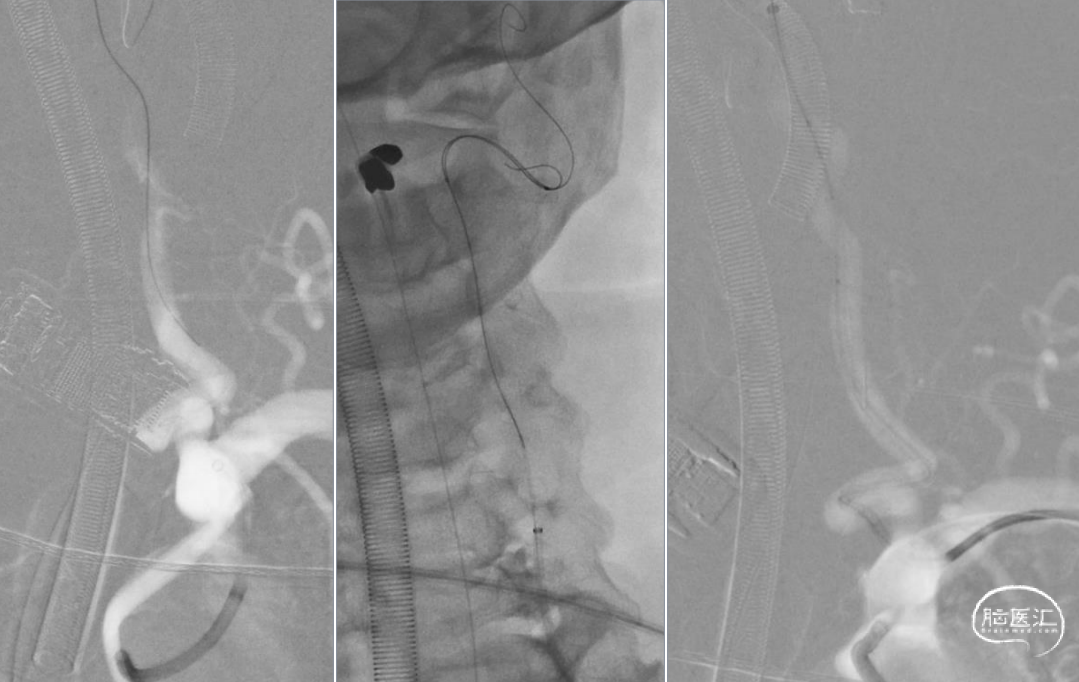

右侧桡动脉入路治疗右侧颈内动脉起始部狭窄

1. 材料:0.035inch的普通导丝、Simmon2、交换导丝、Ballast 088、Emboshield保护伞、Sterling球囊、Acculink6-8/40

2. 同轴+快交换技术

Ballast088+Acculink 6-8/40